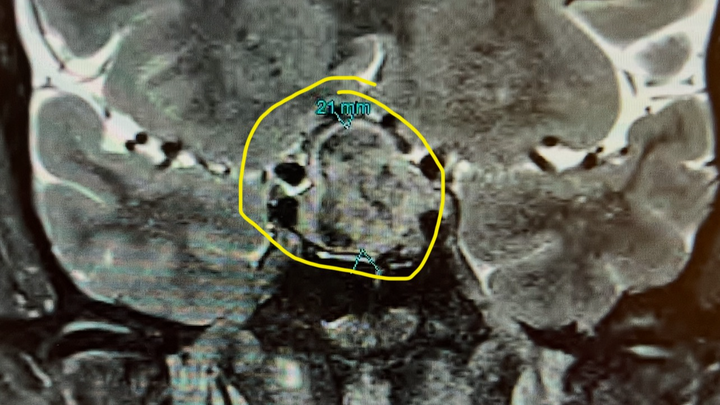

My name is Melissa. I was recently diagnosed with a Pituitary Gland tumor, which I had removed on Monday, the 10th of February. I have now been diagnosed with Acromegaly. As far as I understand, I will battle this for the rest of my life. I will need hormone replacement therapy to do the job my Pituitary Gland can no longer do. I am not familiar with this process; however, I have heard from a few independent people that it is time-consuming to get approved and expensive even when you do.